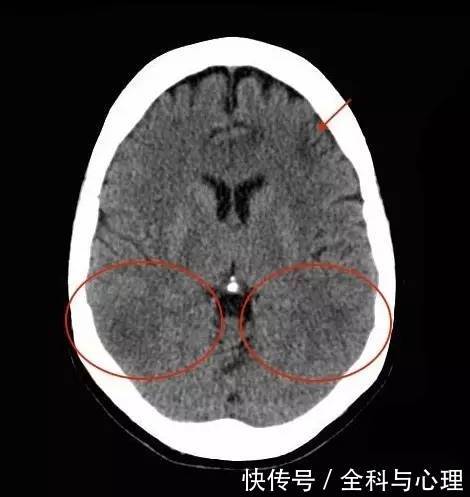

病例学习:肝性脑病的诊断要点

从 MRI 来识别 肝性脑病

急\/慢性肝性脑病丨MRI表现